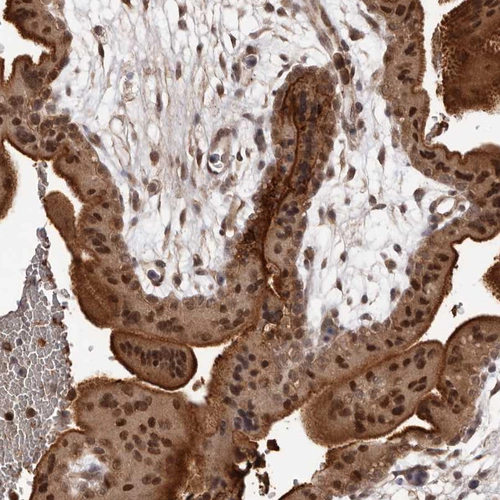

Immunohistochemical staining of human spleen shows moderate nuclear and cytoplasmic positivity in cells in red pulp.